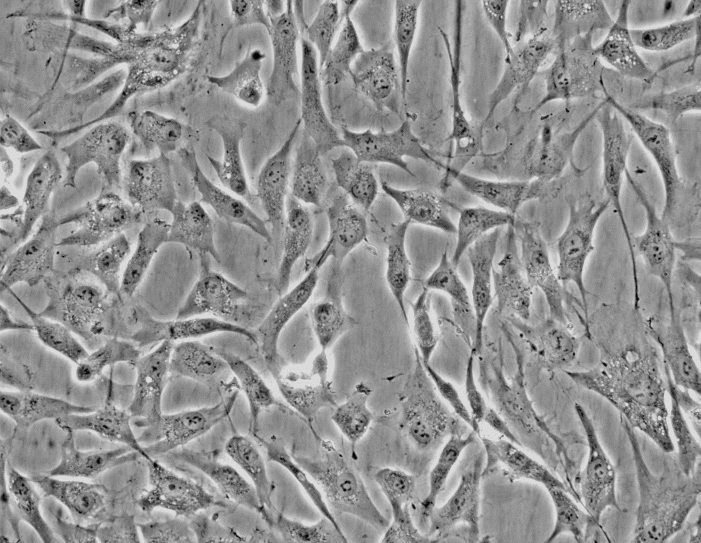

- 生长状态:

贴壁细胞

- 细胞形态:

上皮细胞样

1.产品名称:T-47D(人乳腺管癌细胞)通过STR鉴定

2.组织来源:乳腺;乳房;导管;来自导管癌肋膜渗出液转移灶